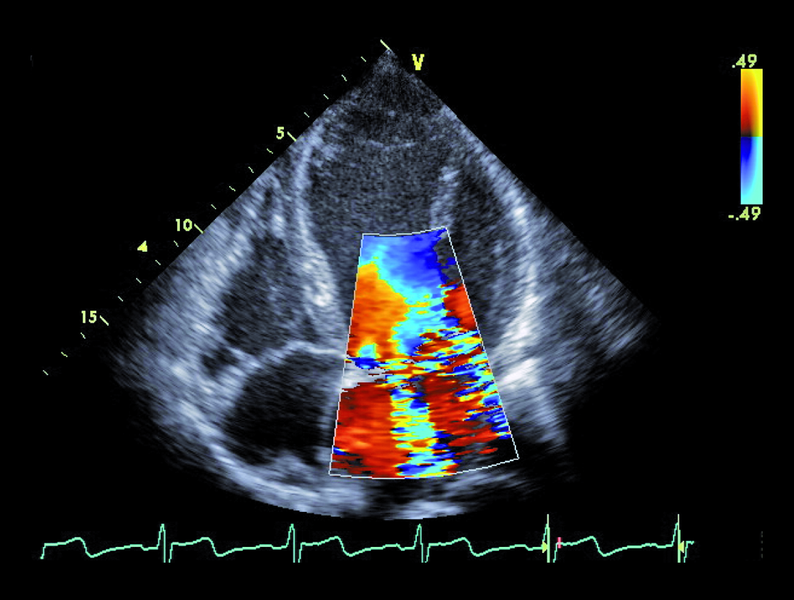

Infekcyjne zapalenie wsierdzia z zajęciem obu natywnych zastawek serca lewego nie budzi w tym przypadku wątpliwości. Proces zapalny może być rozpoznany echokardiograficznie na podstawie linijnych ech mogących odpowiadać rozerwanemu płatkowi zastawki aortalnej oraz na podstawie ciężkiego wypadania płatka zastawki mitralnej (flail), mającego zapewne charakter poinfekcyjny (ryc. 1). Stopień destrukcji zastawki mitralnej w porównaniu z zastawką aortalną wydaje się większy. Między segmentami A2 i P3 pojawia się tętniakowate uwypuklenie, będące pozostałością nacieczenia zapalnego i martwicy tkanki (ryc. 2). Tryb kolorowego doplera ujawnia dwa strumienie niedomykalności – jeden, ekscentryczny wynikający z wypadania przedniego płatka i biegnący wzdłuż bocznej ściany przedsionka (ryc. 3), i drugi pojawiający się w pewnej odległości od miejsca koaptacji, w miejscu, w którym fali zwrotnej trudno się spodziewać, jeśli struktura tkanki budującej płatek jest nienaruszona (ryc. 3, 4). Strumień niedomykalności mitralnej ma w tym wypadku charakter ostry i trafia do nieprzygotowanej i niepowiększonej jamy lewego przedsionka (ryc. 3, 4). Umiarkowana dotychczas niedomykalność aortalna, którą chory przez wiele lat dobrze tolerował, się nasiliła. Dowodem na to jest krótki czas spadku gradientu ciśnień aorta – lewa komora (poniżej 200 ms) (ryc. 5) oraz wyraźny sygnał wsteczny holodiastoliczny w aorcie zstępującej, świadczący o wysokiej wartości frakcji niedomykalności aortalnej (iloraz całki prędkości wypływu krwi na obwód i prędkości fali wstecznej 83%!) (ryc. 6).